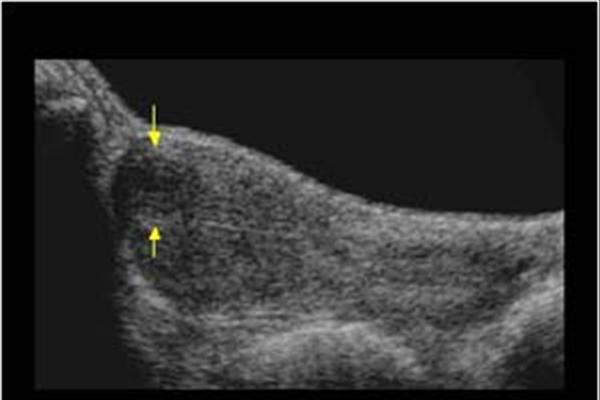

غربالگری و تشخیص زودهنگام بیماریهای پستان از اهمیت بسیاری برخوردار است و سو ...

سونوگرافی سینه و اهمیت غربالگری: راهنمایی جامع برای تشخیص و پیشگیری

غربالگری و تشخیص زودهنگام بیماریهای پستان از اهمیت بسیاری برخوردار است و سونوگرافی سینه یکی از ابزارهای اصلی برای ارزیابی دقیق بافت پستان به شمار میآید. در این مقاله، به اهمیت سونوگرافی سینه در تشخیص، غربالگری و فواید آن در شناسایی بیماریهای پستان میپردازیم.

سونوگرافی سینه یک روش ایمن، بدون درد و مؤثر است که با امواج صوتی، تصاویر دقیقی از بافت داخلی پستان به دست میدهد. این روش بهویژه در خانمهایی که بافت سینههای متراکم دارند، نقش مهمی در تشخیص زودهنگام تودهها و ناهنجاریها ایفا میکند. این ویژگی مهم سونوگرافی، آن را به ابزاری ارزشمند در غربالگری و تشخیص سرطان پستان تبدیل کرده است.

تشخیص تودههای کوچک: سونوگرافی سینه امکان شناسایی دقیق تودههای کوچک را فراهم میکند و به پزشکان کمک میکند تا در مراحل اولیه به تشخیص درست دست یابند.

غربالگری پستانهای متراکم: سینههای متراکم ممکن است در ماموگرافی وضوح کمتری داشته باشند، اما سونوگرافی میتواند به وضوح بافت متراکم را بررسی و ناهنجاریها را شناسایی کند.

تشخیص بیماریهای خوشخیم و بدخیم: سونوگرافی به پزشکان این امکان را میدهد تا بافتهای مشکوک را از هم تمییز دهند و تفاوت بین کیستها و تودههای جامد را مشخص کنند.

غربالگری سینه با سونوگرافی نیاز به آمادگی خاصی ندارد و به راحتی در مراکز رادیولوژی و سونوگرافی قابل انجام است. در این روش، یک ژل مخصوص روی سینه قرار داده میشود و سپس با استفاده از دستگاه سونوگرافی، تصاویر دقیقی از بافت پستان تهیه میشود. این تصاویر به پزشک کمک میکند تا تغییرات موجود در بافت پستان را به دقت ارزیابی کند.